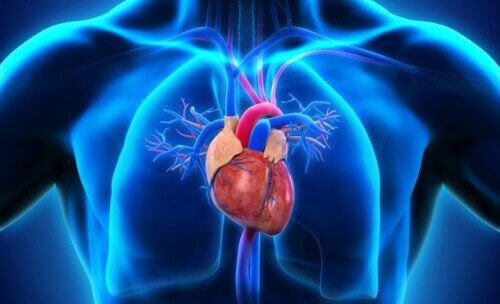

Le tronc artériel commun est une malformation congénitale dans le cadre de laquelle une seule artère mène au coeur, dont les ventricules et les oreillettes ne sont pas bien formés.

En d’autres termes, le tronc artériel commun est une affectation du cœur consistant en une grande artère au lieu de deux artères séparées pour transporter le sang vers les poumons et le reste du corps.

Dans un cœur normal, le sang suit ce cycle : corps-cœur-poumons-cœur-corps. Lorsqu’une personne a un tronc artériel commun, le sang qui quitte le cœur ne suit pas ce cycle normal.

Dans ces cas, le cœur ne comporte pas 4 compartiments séparés correctement mais seulement une cavité. De cette manière, aucun oreillette ni ventricule ne sépare le sang en fonction de son origine et de sa destination. Il n’y a qu’une seule artère commune et il n’y a pas de voie spécifique pour le sang riche en dioxyde de carbone ou le sang oxygéné.